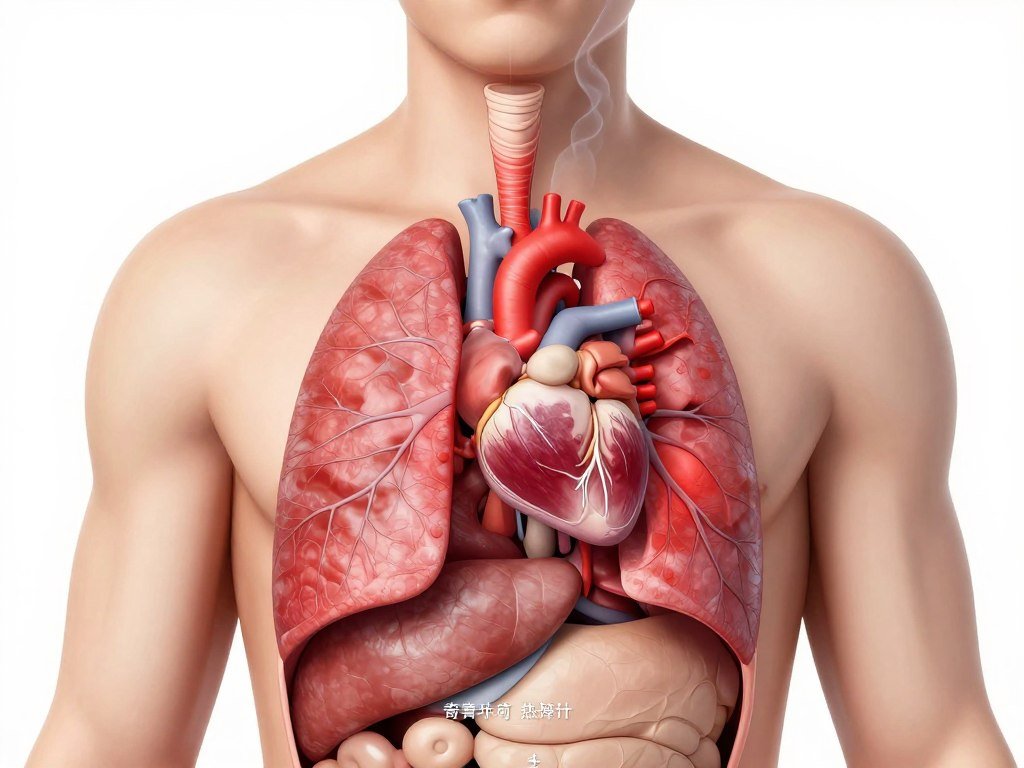

Respiratory Diseases

Cigarette smoke damages lung tissue and airways, leading to chronic conditions that severely limit breathing capacity and quality of life.

Cardiovascular Diseases

Tobacco use significantly elevates risk for various heart and blood vessel conditions that can prove fatal.

- Heart disease and heart attacks

- Stroke and peripheral vascular disease

- Elevated blood pressure and heart rate

- Damaged blood vessel walls